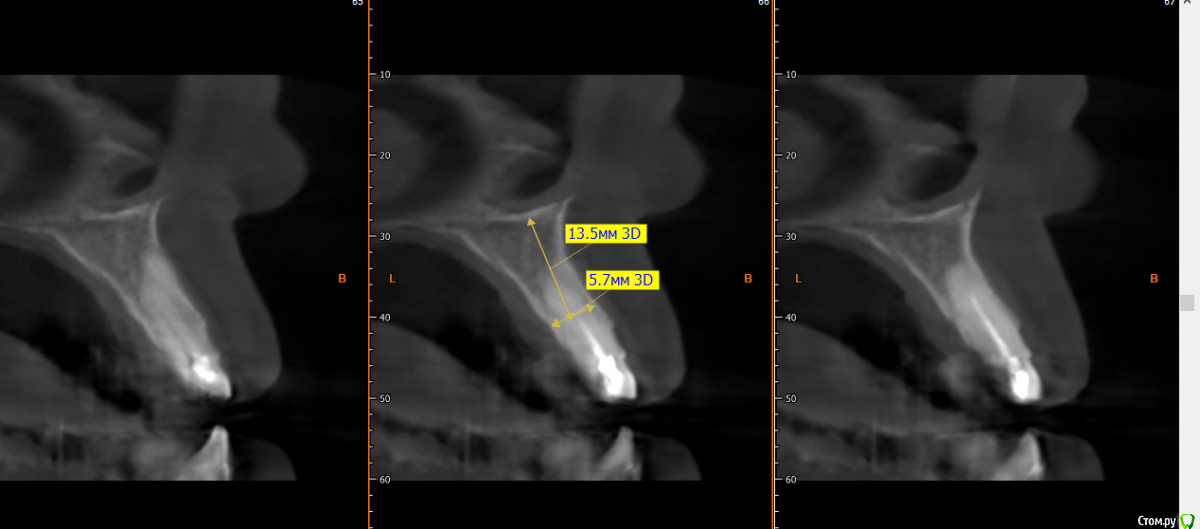

kramer Опубликовано 15 мая, 2019 Поделиться Опубликовано 15 мая, 2019 Коллеги, здравствуйте. Нужен совет. Ситуация: пациентка 70 лет (родственница), давно носила бюгельный протез, и вот одному из опорных зубов пришел конец. КТ ниже, фотографии завтра добавлю. Рассматриваю вариант изготовления несъемного протеза на 4 имплантатах. Опыта все-на-4 нет. Поэтому хотелось бы по крайней мере собрать информацию, возможна ли такая опция. Особенно волнует 2 момента: 1) Отсутствует вертикальная атрофия альвеолярного отростка во фронтальном отделе. Линия улыбки низкая. Предположим, окончательный протез будет м\к или циркон. Означает ли это, что редукцию кости делать необязательно? (правда там и редуцировать особо некуда). 2) В области 14 и 24 ширина гребня 3,5-4 мм. Что делать с этим? Оставлять пришеечную часть винта не покрытым костью небно или пытаться каким-то образом конденсировать кость? 14122224 Ссылка на комментарий

Smileee Опубликовано 16 мая, 2019 Поделиться Опубликовано 16 мая, 2019 Я бы везде установил 3.5, в области 24 немного редуцировал бы кость по вертикали. Все импланты максимально небно. Ссылка на комментарий

kramer Опубликовано 17 мая, 2019 Автор Поделиться Опубликовано 17 мая, 2019 не надо там ничего редуцировать, само резорбируется после удаления на 1-2 мм. все на 4-х и счастья вашей родственницеСпасибо, что делать с узким гребнем? Максимально глубить? Ссылка на комментарий